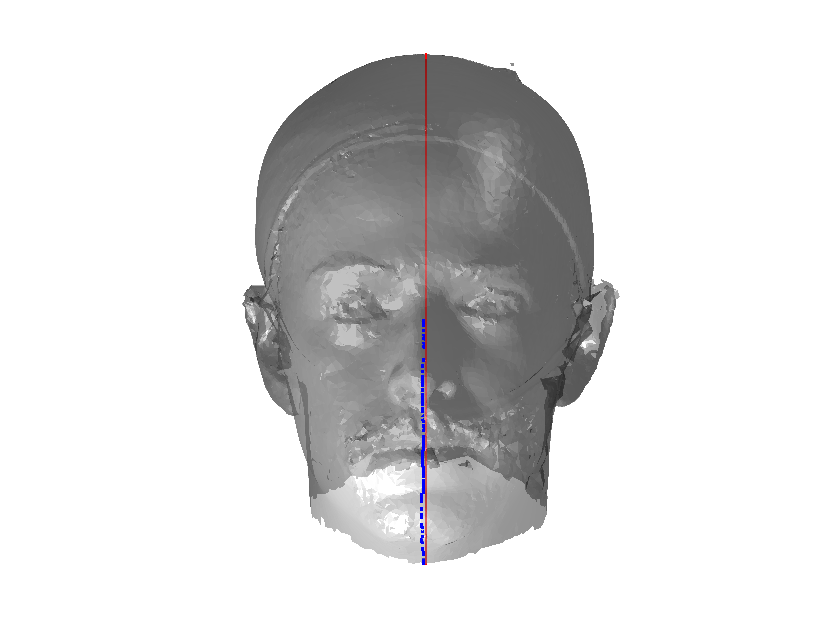

Pose is normalised using the ECN method, and relies on the symmetry plane, ellipse centre and nasion position, as shown in Fig. 25. We then find a set of pseudo-landmarks on the cranial surface by 3D ray projection over a predefined set of angles, as shown in Fig. 26. The same processes are applied to a template mesh of the human head, so that it has the same set of both face and cranium landmarks.

The template mesh is then warped in a global affine sense, as shown in Fig. 27 to minimise the least-squares error between the two sets of landmarks, when the head scan is fixed in its canonical poose. After this initial stage, landmarks and pseudo-landmarks are used in the same way as any other mesh vertex, as they are potentially noisy, as seen in earlier results analysis. This contrasts with Amberg et al’s [11] approach where the influence of landmarks is gradually faded out.